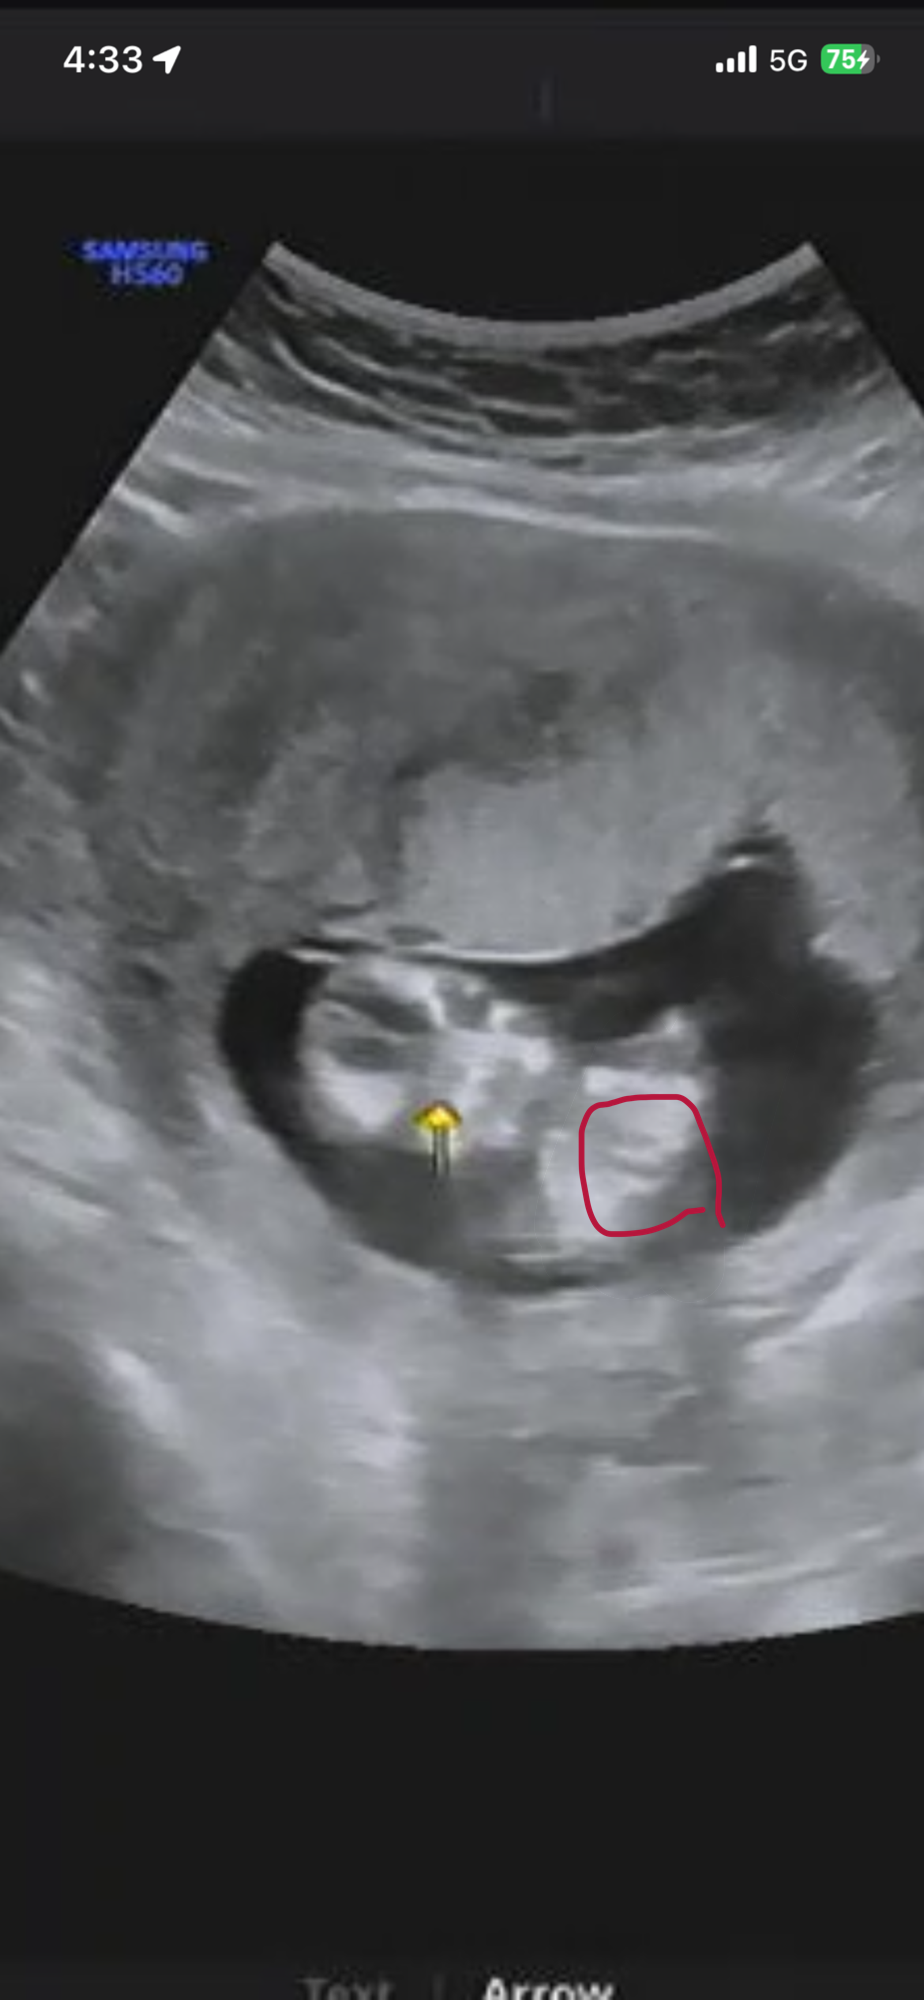

12주6일

뭘로 보이나요?